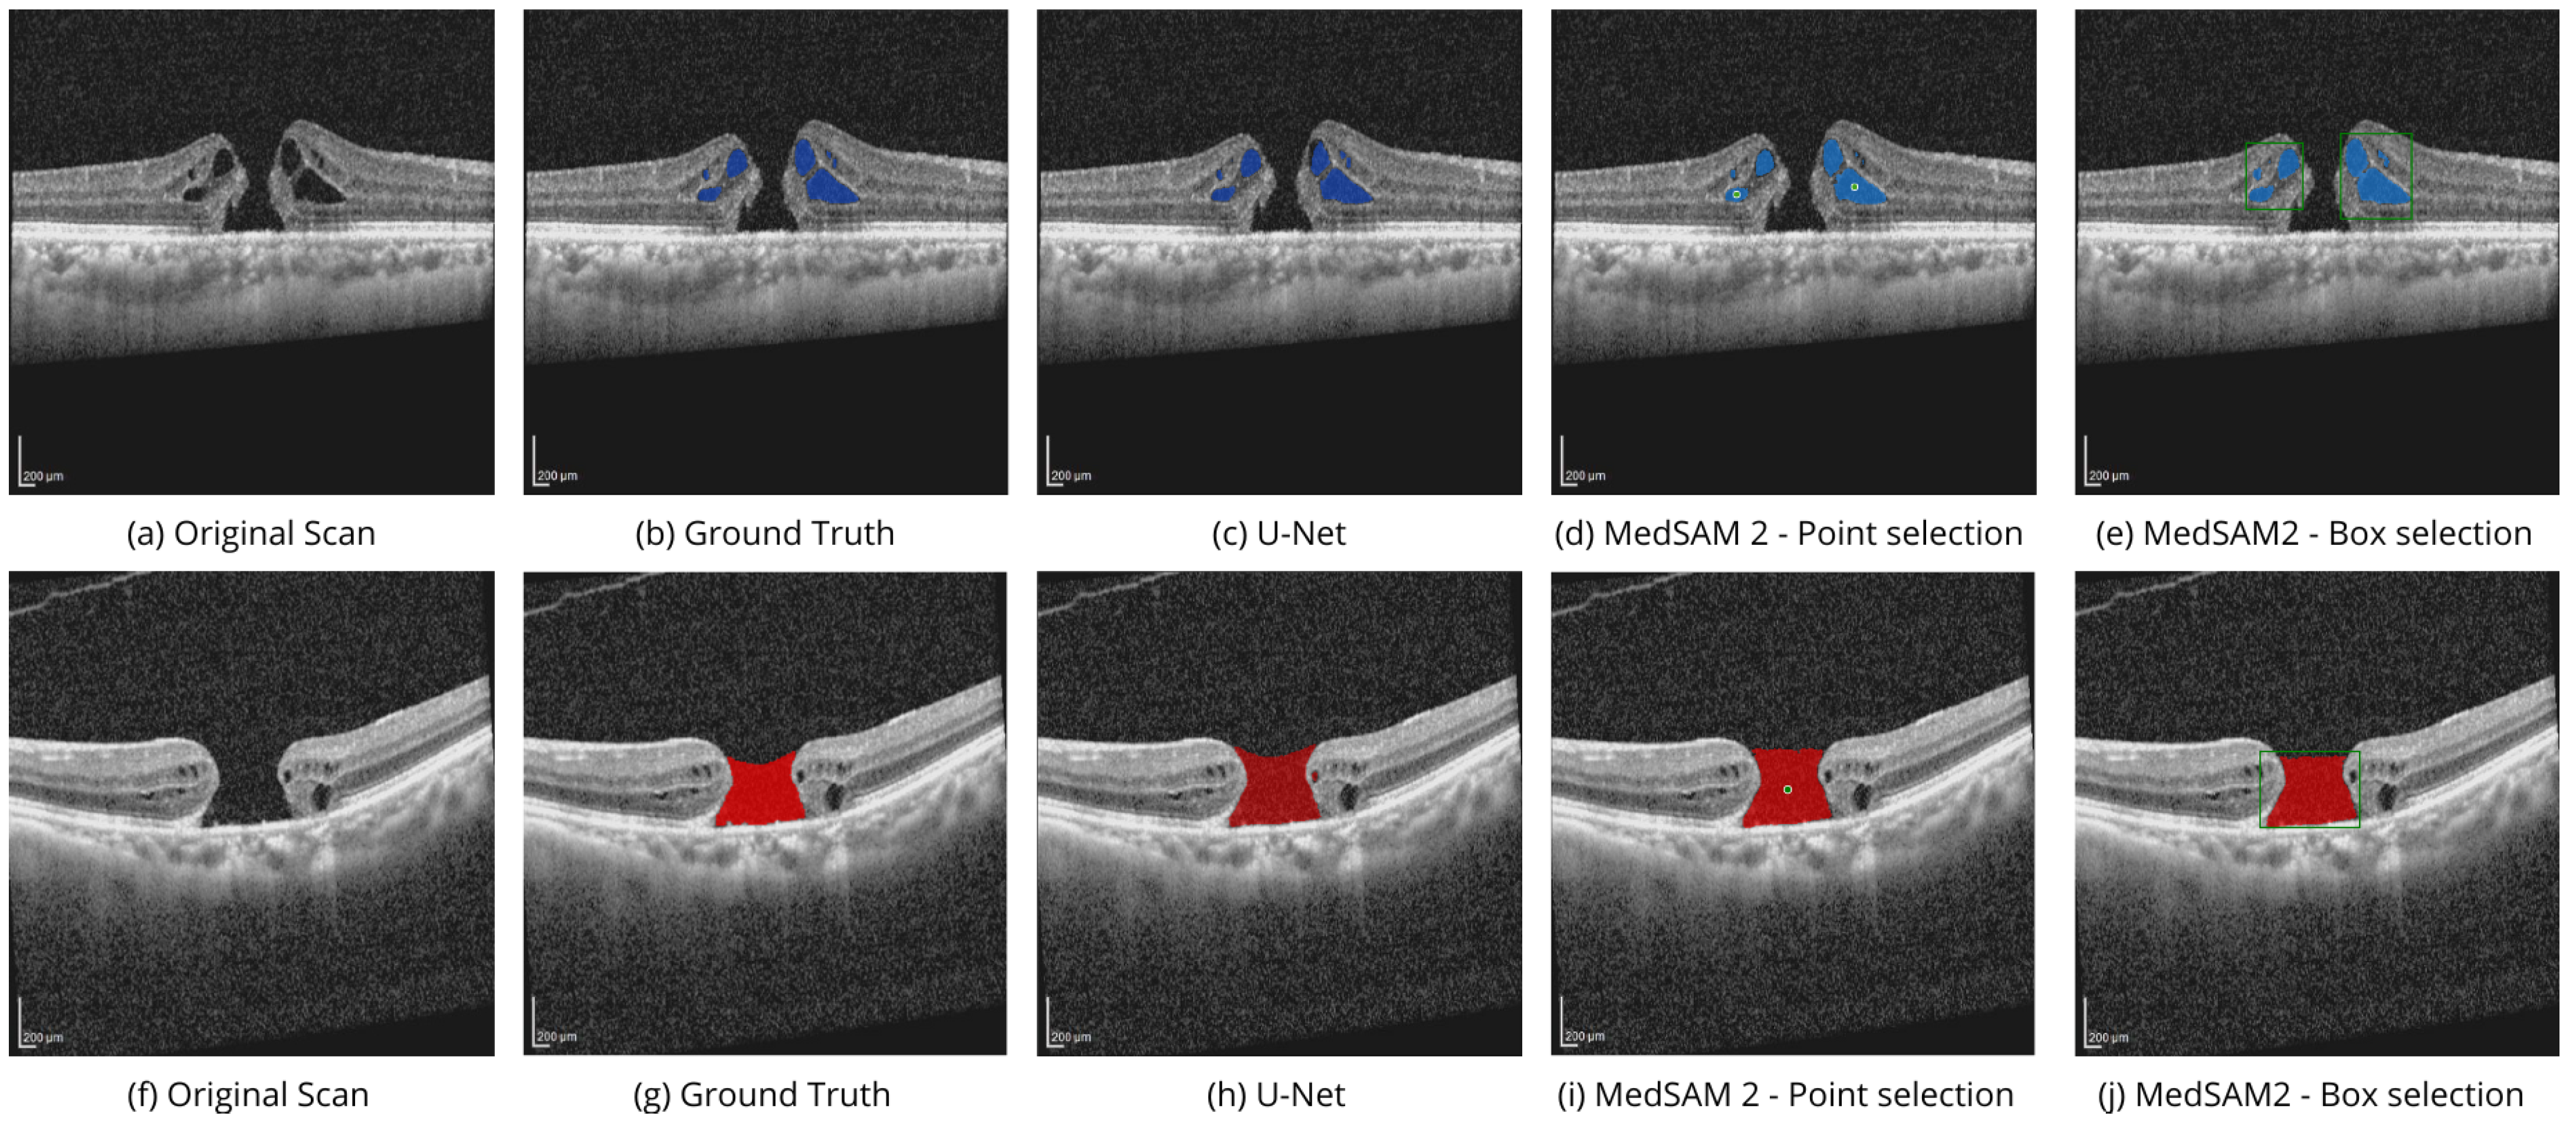

| Experiment | OIMHS | AROI | ||||||

| MH | IRC | IRF | PED | |||||

| IoU 1 | Dice | IoU | Dice | IoU | Dice | IoU | Dice | |

| SAM 2—Point Selection | 0.201 | 0.335 | 0.109 | 0.196 | 0.172 | 0.293 | 0.102 | 0.185 |

| SAM 2—Box Selection | 0.214 | 0.352 | 0.113 | 0.203 | 0.175 | 0.298 | 0.112 | 0.201 |

| U-Net | 0.771 | 0.871 | 0.762 | 0.865 | 0.759 | 0.863 | 0.784 | 0.879 |

| MedSAM 2—Point Selection | 0.814 | 0.897 | 0.827 | 0.906 | 0.799 | 0.888 | 0.809 | 0.895 |

| MedSAM 2—Box Selection | 0.840 | 0.913 | 0.821 | 0.902 | 0.791 | 0.884 | 0.832 | 0.909 |